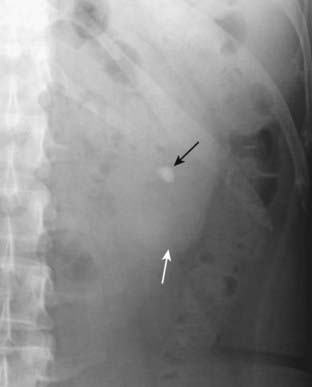

image

Figure 16-8 Imaging findings of ureteral calculi, three different patients.

A, A calcified stone is seen in the left ureter (solid white arrow). B, Hydronephrosis is present on the right (dotted white arrow) with overall enlargement of the right kidney (solid white arrow). C, There is considerable perinephric stranding (dotted white arrows) and fluid that has leaked from the kidney (solid white arrow), most likely from a rupture of one of the renal fornices.